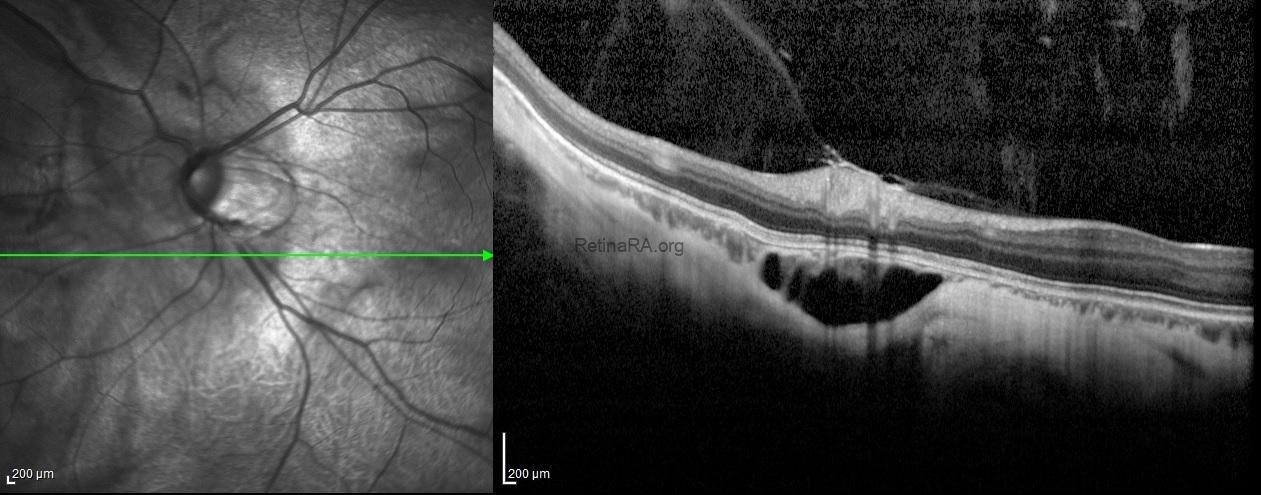

Spectral-domain optical coherence tomography showed the choroidal neovascular membrane scar without any subretinal or intraretinal fluid in additon to posterior staphyloma in the right eye. For the left eye, the OCT-scan passing throught the lesion under the optic disc exhibited an intrachoroidal space with a hyporeflective appearance below the normal plane of retinal pigment epithelium with normal Bruch’s membrane and retinal layers over the lesion.

A 27-year-old male patient applied for routine eye examination. He underwent three intravitreal injections in the right eye 2 year ago and had no history of previous ocular surgery. On ocular examination, the BCVAs were 20/200 with the correction of -12.00 diopters in the right eye and 20/30 with the correction of -14.00 diopters in the left eye. Intraocular pressures were within normal limits in both eyes and no pathology was observed in the anterior segment examination.